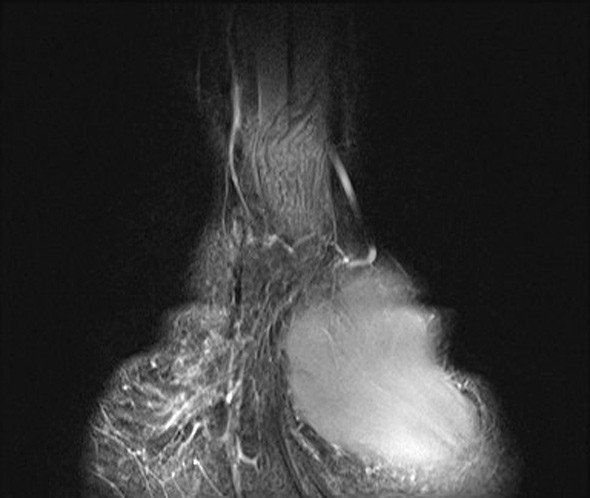

En tidligere frisk jente i tenårene ble henvist til håndkirurgisk avdeling med en kul på bøyesiden ved venstre håndledd. Denne var blitt oppdaget av mor rundt syv år tidligere og var etter hvert blitt økende smertefull. Pasienten beskrev overfølsomhet for berøring og nummenhet i tommel, peke-, lang- og ringfinger. Perkusjon over tumor ga utstrålende smerter og økt nummenhet i de samme fingrene. MR-undersøkelse viste en fortykket medianusnerve med utseende som en kabel på grunn av fibrøs fortykkelse av peri- og endonevrium og økt mengde fett som separerer de ca. 15 nerveaksonene (bilder på nett). Tumorens utbredelse var ca. 10 cm. Tilstanden ble diagnostisert som et lipofibromatøst hamartom på grunn av MR-funnene, som angis som patognomoniske for tilstanden (1).

Det ble gjort eksplorasjon av tumor og dekompresjon av nerven i karpaltunnelen. Bildet viser tumoren, som på det tykkeste hadde 3 × større diameter enn en normal nerve. Ved kontroll to og seks måneder senere hadde pasienten de samme smerteplagene som før operasjonen, men følesansen i fingrene var forbedret. Nevrografi etter to måneder viste moderat aksonal og demyeliniserende sensorimotorisk affeksjon av medianusnerven i håndledds- og håndrotsnivå, tydende på kompresjonsnevropati. EMG-undersøkelse viste sparsom denervasjonsaktivitet og funn som ved gjennomgått reinnervasjon. Det var ingen tidligere undersøkelser som man kunne sammenligne med.